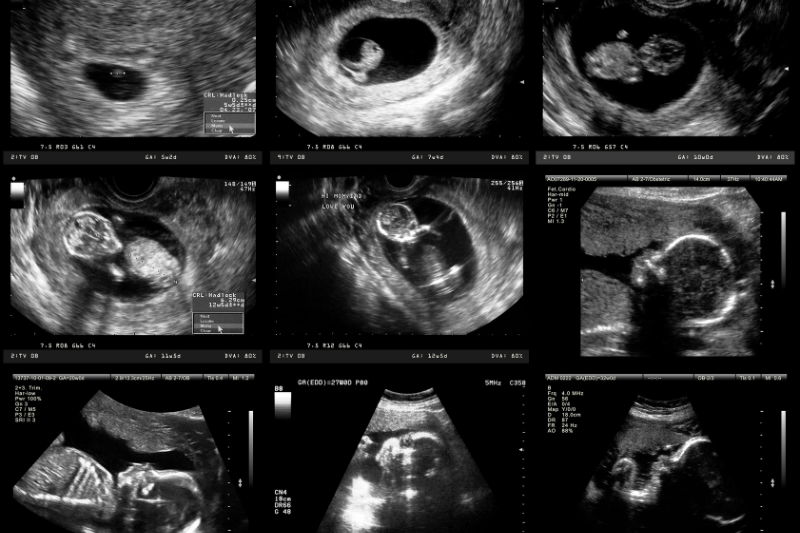

Kombinovani skrining testa u prvom trimestru trudnoće (između 11 i 14 nedelje trudnoće) na aneuploidije (Daunov, Edvardsov, Patau i slični sindromi) (u našoj populaciji se odomaćio naziv Dabl test), se savetuje svim trudnicama.Test se satoji iz dva dela, ultrazvučnog pregleda bebe sa merenjem debljine vratnog nabora bebe (tzv Nuhalne transluscence ili NT-a) i ispitivanjem drugih ultrazvučnih parametara, kao i biohemijskog dela u kome se iz uzroka krvi trudnice određuju vrednosti biohemijskih parametara iz krvi (slobodnog β-hCG i PAPP-A). Pouzdanost ovog testa u otkrivanju Daunovog sindroma je 90%, Edvardsovog i Patau sindroma oko 75% (*izvor- Feto Maternal Foundation, London UK). Ovaj ultrazvučni pregled omogućava da se otkrije i značajan broj velikih anomalija ploda, ukoliko postoje.

Tripl test je prenatalni, neinvazivni, skrining test drugog trimestra trudnoće, koji se radi između 15. i 20. nedelje trudnoće. Ovaj test ukazuje na verovatnoću postojanja nekih aneuploidija ali i defetkta neuralne cevi. U testu se kombinuju podaci dobijeni ultrazvučnim pregledom i analizom biohemijskih parametara koji se određuju iz krvi trudnice (AFP- alfafetoprotein, HCG-humani horioni gonadotropin i nekonjugovani estriol).Kvadripl test je skrining test koji se radi između 16. i 22. nedelje trudnoće. Kao i tripl test, ovaj test kombinuje podatke dobijene ultrazvukom i analizom biohemijskih parametara.